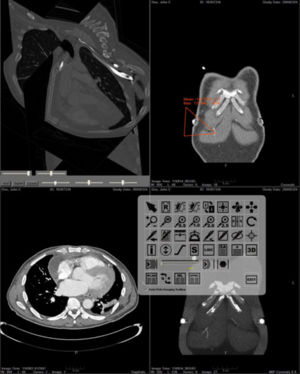

Developmental Response to Cold Stress in Cranial Morphology of Rattus: Implications for the Interpretation of Climatic Adaptation in Fossil Hominins

Publication: Proc. R. Soc. B (2006) 273, 2605–2610. PDF

Authors: Todd C. Rae, Una Strand Viðarsdottir, Nathan Jeffery A. Theodore Steegmann Jr

Institution: Evolutionary Anthropology Research Group, Department of Anthropology, University of Durham, 43 Old Elvet, Durham DH1 3HN, UK

Background/Purpose: Adaptation to climate occupies a central position in biological anthropology. The demonstrable relationship between temperature and morphology in extant primates (including humans) forms the basis of the interpretation of the Pleistocene hominin Homo neanderthalensis as a cold-adapted species. There are contradictory signals, however, in the pattern of primate craniofacial changes associated with climatic conditions. To determine the direction and extent of craniofacial change associated with temperature, and to understand the proximate mechanisms underlying cold adaptations in vertebrates in general, dry crania rom previous experiments on cold- and warm-reared rats were investigated using computed tomography scanning and three-dimensional digitization of cranial landmarks. Aspects of internal and external cranial morphology were compared using standard statistical and geometric morphometric techniques. The results suggest that the developmental response to cold stress produces subtle but significant changes in facial shape, and a relative decrease in the volume of the maxillary sinuses (and nasal cavity), both of which are independent of the size of the skull or postcranium. These changes are consistent with comparative studies of temperate climate primates, but contradict previous interpretations of cranial morphology of Pleistocene Hominini.

Grant Support: None. Prof. Steegmann supplied the materials, and the time on the pQCT machine was graciously donated by Prof. Tim Skerry of the Royal Veterinary College, London.